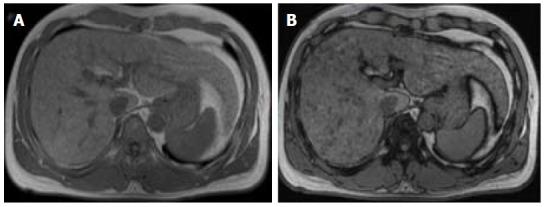

Hepatocellular carcinoma (HCC) usually develops in the setting of chronic liver disease. In the adequate clinical context, both multiphasic contrast-enhanced CT and magnetic resonance imaging are non-invasive modalities that allow accurate diagnosis and staging of HCC, although the latter demonstrates greater sensitivity and specificity. Imaging criteria for HCC diagnosis rely on hemodynamic features such as hyperenhancement in the arterial phase and washout in the portal or equilibrium phase. However, imaging performance drops considerably for small (< 20 mm) nodules because their tendency to exhibit atypical enhancement patterns. In order to improve accuracy in the diagnosis and staging of HCC, particularly in cases of atypical nodules, ancillary features, ., imaging characteristics that modify the likelihood of HCC, have been described and incorporated into clinical reports, especially in Liver Imaging Reporting and Data System. In this paper, ancillary imaging features will be reviewed and illustrated.

肝细胞癌(HCC)通常在慢性肝病背景下发生。在适当的临床背景下,多期对比增强CT和磁共振成像都是非侵入性检查方法,可实现HCC的准确诊断和分期,尽管后者具有更高的敏感性和特异性。HCC诊断的影像学标准依赖于血流动力学特征,如动脉期强化和门脉期或平衡期廓清。然而,对于小(<20mm)结节,其成像表现会显著下降,因为它们倾向于表现出非典型强化模式。为提高HCC诊断和分期的准确性,特别是非典型结节病例,已描述了辅助特征,即改变HCC可能性的影像学特征,并将其纳入临床报告,尤其是肝脏影像报告和数据系统。本文将对辅助影像学特征进行综述和说明。